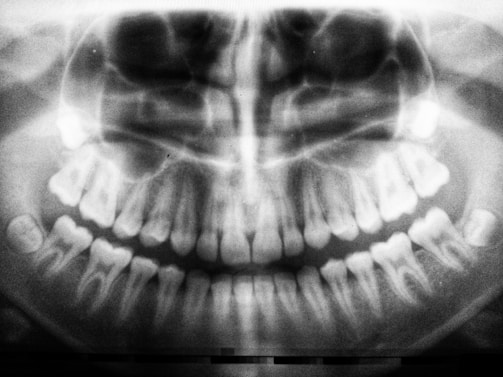

Dental X rays

The Dental X-rays service at Ultra Cosmetic Medical Center offers advanced imaging solutions, including OPG (Orthopantomogram) and 3D X-ray procedures. These state-of-the-art techniques provide comprehensive views of teeth, jaws, and surrounding structures, assisting our dental professionals in accurate diagnosis and treatment planning. The OPG captures a single image of the entire mouth, which is essential for detecting dental issues, while 3D X-rays enable a detailed examination of complex areas, facilitating precise interventions. Our experienced team ensures that the process is comfortable and efficient, using the latest technology to minimize radiation exposure. Schedule your appointment today to take the first step towards optimal dental health with our reliable X-ray services.